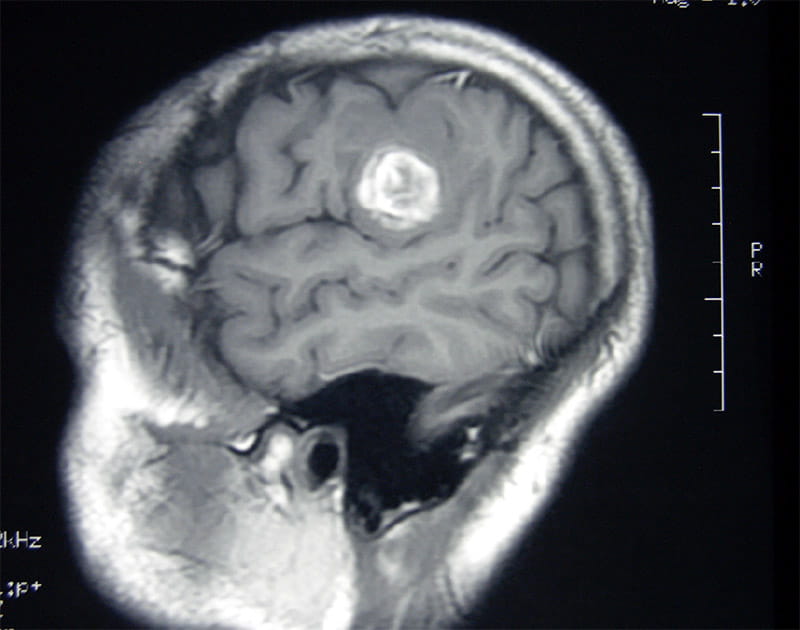

A brain scan showed the tumor. Had it grown a few more millimeters, it could've been fatal. Still, Schwartz's life remained in jeopardy because, by all indications, the tumor was most likely cancerous.

A scan of Lawrence Schwartz's brain, with the tumor highlighted. (Photo courtesy of Lawrence Schwartz)

A scan of Lawrence Schwartz’s brain, with the tumor highlighted. (Photo courtesy of Lawrence Schwartz)